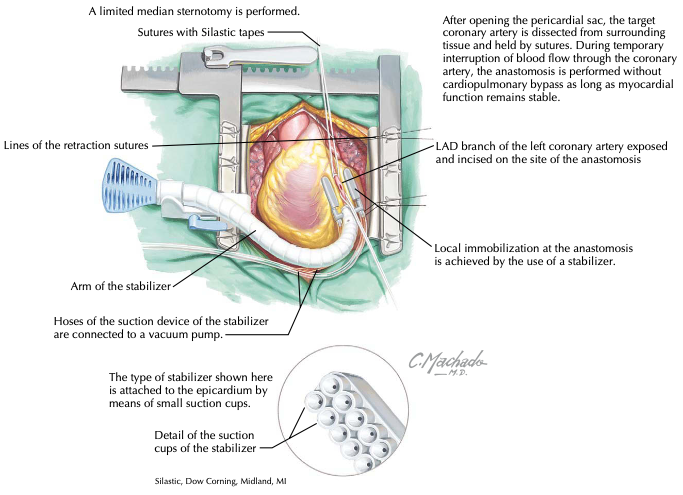

Historicamente, o desenvolvimento gradativo da cirurgia cardiovascular foi intimamente relacionado à cirurgia de revascularização do miocárdio (RM) no tratamento…